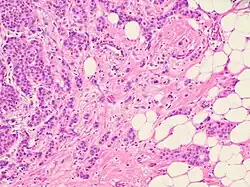

Two types of migrating tumor cells, mesenchymal (fibroblast-like) and amoeboid, can be observed in various patterns of cancer cell invasion. This article describes the key differences between the variants of cancer cell migration, the role of epithelial-mesenchymal and related transitions, as well as the significance of different tumor factors and stromal molecules in tumor invasion. Morphological manifestations of the invasion patterns are characterized by a variety of tissue (tumor) structures.[2]

Two distinct patterns of invasive growth are distinguished based on specific morphological and molecular genetic parameters: single-cell migration and collective cell migration. The migration type is predominantly influenced by characteristics of the tissue microenvironment, and is dependent on molecular changes within the tumor cells.

In the case of collective migration, cancer cells, being a part of the tumor mass or detaching from it in the form of multicellular groups, penetrate into the surrounding tissues and form thin, short chords, clusters, stripes and wide fields, as well as structures with lumen, that indicate a wide variety of structural elements involved in tumor invasion.[2]

Collective migration is characterized by the migration of whole cell groups interconnected by cadherins and intercellular gap junctions. A moving cell group has a “leading edge” or “leading front” that uses integrins and proteases. Observable differences exist in the expression of the genes and morphology between the “leader” cells forming the leading edge and the “follower” cells that are located behind them, at the “trailing edge”.[2] The cell shape of the “leaders” often resembles mesenchymal cells and is characterized by a less pronounced ordering and structural organization, while the “followers” tend to form more tightly packed, rosette-like tubular structures with tight intercellular contacts.[2]

Single cell invasion is distinguished by individual tumor cells invading the surrounding tissues independently of each other. In this type of tumor invasion, single cell migration can occur via two different movement types: mesenchymal and amoeboid. These movement types are highly plastic and can shift from one type of migration to the other (from mesenchymal to amoeboid and vice versa). These transitions usually occur upon changes in the activity of certain cell molecules when tumor cells have to adapt to the peculiarities of the microenvironment.[2]

This type of migration is typical of keratinocytes during reparative regeneration, endotheliocytes, smooth muscle cells, and fibroblasts. Since malignant cells that use mesenchymal-type movement lose their epithelial polarity and adopt an elongated spindle shape resembling that of fibroblasts, this type of invasion is also referred to as 'fibroblast-like' migration. Mesenchymal invasion has been detected during the development of melanoma, fibrosarcoma, glioblastoma, and other malignancies.[2]

Despite the structural diversity of the primary breast tumor, five main types of morphological structures can be distinguished: alveolar, trabecular, tubular and solid structures, and discrete groups of tumor cells. The alveolar structures are tumor cell clusters of round or slightly irregular shape. The morphology of the cells that form this type of structures varies from small cells with moderate cytoplasm and round nuclei to large cells with hyperchromatic nuclei of irregular shape and moderate cytoplasm. The trabecular structures are either short, linear associations formed by a single row of small, rather monomorphic cells or wide cell clusters consisting of two rows of medium-sized cells with moderate cytoplasm and round normochromic or hyperchromatic nuclei. The tubular structures are formed by a single or two rows of rather monomorphic cells with round normochromic nuclei. The solid structures are fields of various sizes and shapes, consisting of either small cells with moderate cytoplasm and monomorphic nuclei or large cells with abundant cytoplasm and polymorphic nuclei. Discrete groups of cells occur in the form of clusters of one to four cells with variable morphologies.[2]

The different morphological structures of breast tumors correspond to certain types of invasion. Therefore, alveolar, trabecular, and solid structures that are characterized by the presence of cell-cell contacts may be referred to morphological manifestations of collective migration, while discrete groups of tumor cells may be referred to manifestations of individual migration. The first batch of data obtained in a study of the expression of cell adhesion genes confirms this hypothesis. For example, there was a decrease in the activity of the genes of cadherins, which are responsible for cell-cell contacts, in the order: solid – alveolar and trabecular structures – discrete groups of tumor cells. In this case, the number of expressed genes of integrins involved in the adhesion of tumor cells to the extracellular matrix was reduced in the order: solid and alveolar – trabecular structures – discrete groups of tumor cells.[2]